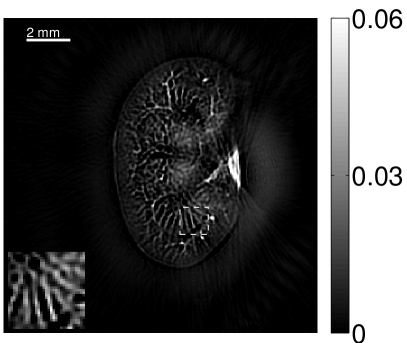

VI-E Results: kidney phantom

The images and EIRs reconstructed by use of the VP algorithm that was based on the 2D imaging model that neglected the SIR are shown in Figures 15 and 16. The latter figure contains results corresponding to different values for the regularization parameter . From Fig. 15, it can be observed that use of the conventional iterative method that utilized the measured EIR resulted in distortions and loss of details in the reconstructed images. Use of the VP algorithm improved the contrast and the details in the reconstructed images (Fig. 15(c) and 16(a)). Furthermore, the images reconstructed by use of the VP algorithm had a more uniform background.

In Figure 17, the results corresponding to use of the 3D imaging model that incorporated SIR effects are shown. The EIR estimated by the VP algorithm is also shown. In Figure 18, images and EIRs reconstructed by use of the VP algorithm with different regularization parameters values are shown.

Similar to the case described above where the transducer SIR was neglected, these results reveal that use of the VP algorithm can produce images with a cleaner background and enhanced spatial resolution than yielded by use of a conventional iterative algorithm that employed the measured EIR. For example, detailed information regarding the vessels near the organ’s periphery was better preserved by the VP algorithm than by the conventional iterative algorithm. These images corroborate our assertion that the VP algorithm can significantly reduce the artifacts and distortions in the reconstructed image. It is also worth pointing out that, unlike the numerical phantom studies, the artifacts and distortions in the images may be caused not only by the inaccurate EIR but also by other factors, such as neglecting acoustic heterogeneities and the variation of the EIRs among the elements of the transducer array. In such cases, the EIR estimated by the VP algorithm represents an effective system impulse response that minimizes the inconsistency between the measured data and the imaging model.